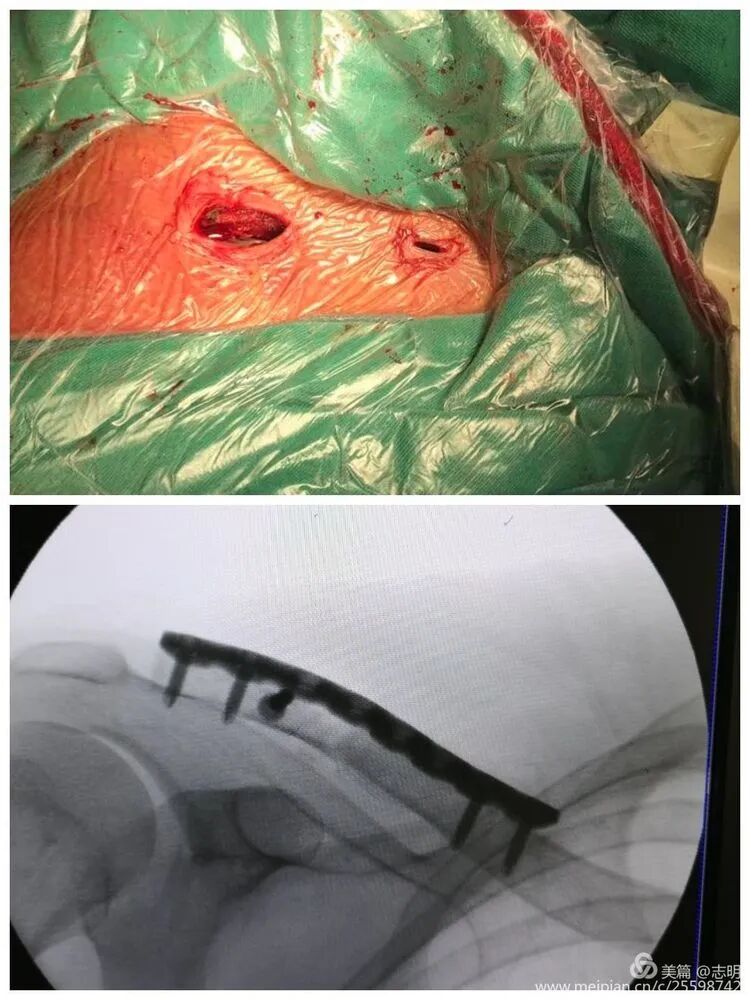

1. Incision Planning and Skin Marking

- Palpation and Marking: Carefully palpate the clavicle along its entire length, identifying the fracture site and the proposed course of the plate. Mark the skin corresponding to the ends of the selected plate, typically at the second screw hole from each end.

-

Small Incisions:

Make two small transverse or oblique incisions (approximately 1-2 cm each) directly over the marked points on the anterosuperior aspect of the clavicle. These incisions should be just large enough to allow screw insertion and passage of instruments. The choice of anterosuperior plating reduces prominence and potential irritation of supraclavicular nerves compared to purely superior plating.

- Palpation and Clavicle Outline: Begin by thoroughly palpating the entire length of the clavicle, meticulously identifying the precise fracture site and the anticipated course of the chosen plate. Mark the overlying skin to delineate the clavicular outline.

Incision Placement:

Based on the pre-operative templating, mark the skin for two small incisions, typically positioned over the second screw hole from each end of the selected plate. These incisions, approximately 1-2 cm in length, are usually oriented transversely or obliquely on the anterosuperior aspect of the clavicle. The chosen anterosuperior plate trajectory is preferred over a purely superior one to mitigate hardware prominence and minimize the risk of irritation to the supraclavicular nerves. Ensure the incisions are just sufficient to accommodate screw insertion and the passage of necessary instruments.

(Image showing plate used for surface marking to define incision points).